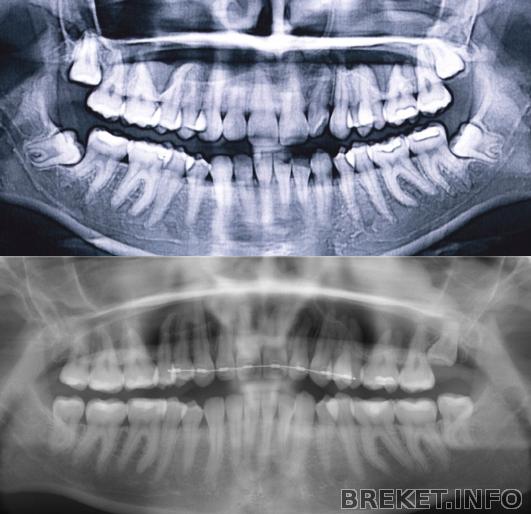

С другой стороны, восьмёрки - дело непредсказуемое: у меня обе нижние лежали буквально, но вышли и прекрасно встали в ряд. Скученности не прибавилось.

Mel, первое фото - осень 2007 года, второе - осень 2012. В 2007 три восьмёрки начали прорезываться, к началу 2011 они уже вышли и встали в дугу, но у меня ОПГ за этот период нет.

kira_v, да, у тебя очень аккуратно они вписались,хотя пока в десне были, все не столь радужно казалось)